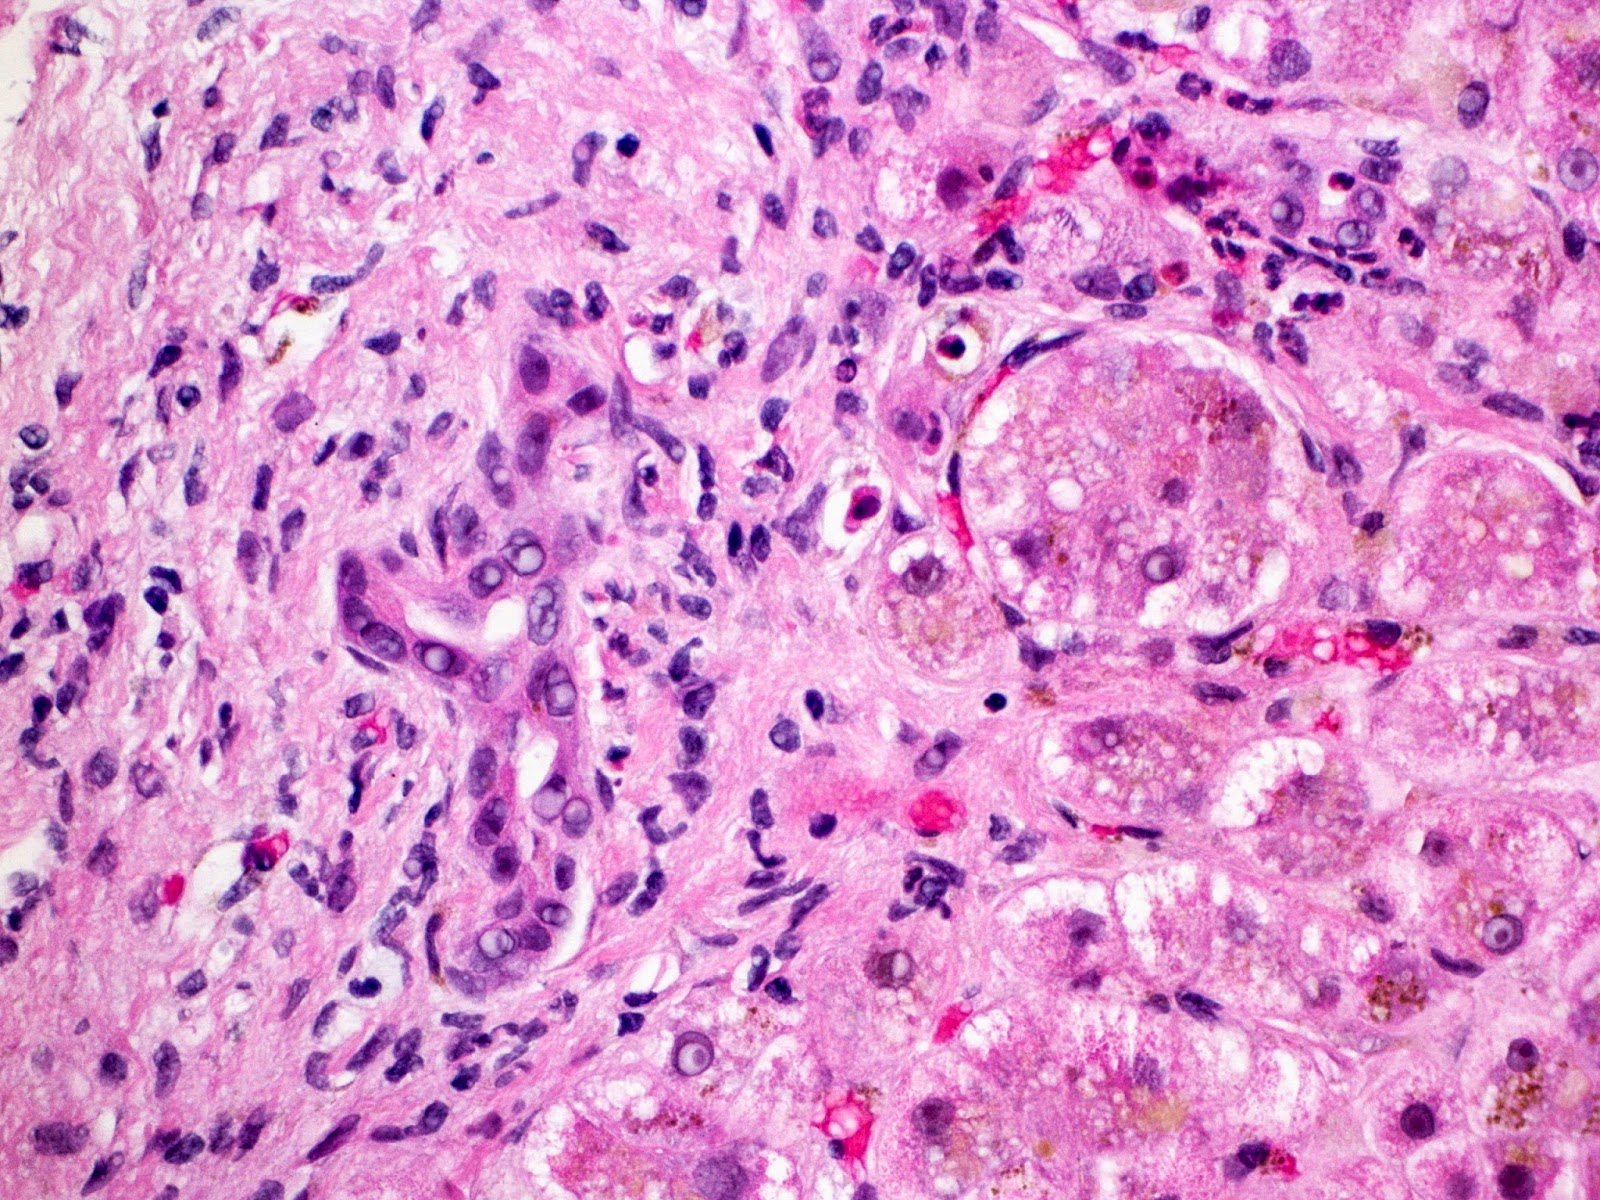

Microscopic Images

Figure 1 shows a large portal area with several vascular profiles and lack of interlobular bile duct. Figure 2 shows the only bile duct identified on multiple levels. This duct shows features of injury including loss of nuclear polarity and nuclear hyperchromasia.

Figure 3 shows marked canalicular cholestasis.

Figure 4 is the keratin 19 stain confirming a lack of interlobular bile duct and essentially no ductular reaction.

Figures 5 and 6 show portal-portal bridging fibrosis at least.

The paucity of interlobular bile ducts and lack of ductular reaction raises several possibilities. The top of the list in this setting would be chronic graft versus host disease (GVHD). However, advanced fibrosis with chronic GVHD is rarely described. From the available clinical records, this patient has a history of chronic skin and liver GVHD that has responded well to immunosuppression in the past. Furthermore, the patient intermittently electively takes herself off immunosuppressive therapy with resultant flares, as happened in this case.